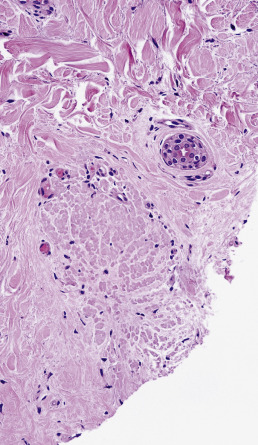

Diagnostic biopsies demonstrate lichenoid interface dermatitis of the follicular unit and sometimes the intervening epidermis. The entire fibrous tract may be filled with cytoid bodies ( Fig. 33.14 ). The changes usually occur focally and may be best visualized with serial vertical sections. Perifollicular mucinous fibrosis is common, and focal perifollicular lymphoid infiltrates tend to involve the infundibulum (infiltrates of LE tend to involve isthmus). DIF may be negative or may reveal cytoid bodies and shaggy linear fibrin at the DEJ.